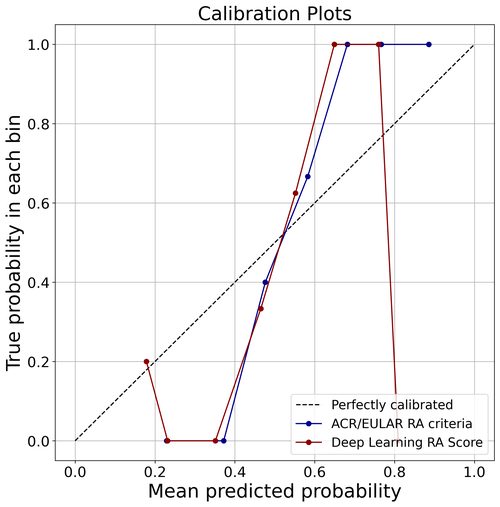

当科では、日常診療から生まれるクリニカルクエスチョンを大切にし、臨床研究へとつなげています。特に力を入れているのが、深層学習(ディープラーニング)を用いた関節リウマチの診断支援システムの開発です。

従来のACR/EULAR分類基準とは異なるアプローチで、臨床データから直接RA診断を支援するスコアリングシステムを構築。そのキャリブレーションとROC解析の結果は、新たな診断支援ツールとしての可能性を示しています。

専攻医もこうした研究プロジェクトに参画でき、学術発表や論文執筆の機会を得ることができます。